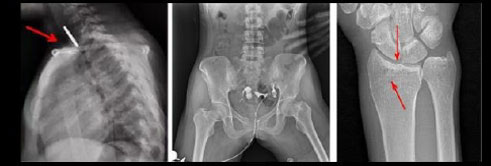

- Функция Автоматического сшивания изображений, позволяющая формировать предоперационные хирургические планы и оценивать послеоперационные последствия, такие как сколиоз и нагрузка на костные ортопедические изделия, протезирование колена и эндопротезирование тазобедренного сустава (данная функция опциональна и предоставляется по предварительному запросу)

Рентгенологические исследования: рентгенография больших переломов костей и масштабное физическое рентгенографическое обследование, флюороскопия всех частей тела (грудная клетка, живот и т.д.), пищеводная ангиография, ангиография верхних отделов желудочно-кишечного тракта, полная ангиография желудочно-кишечного тракта, холангиография, Т-образная холангиография, ЭРХПГ, внутривенная пиелография, гистеросальпингография и т.д.